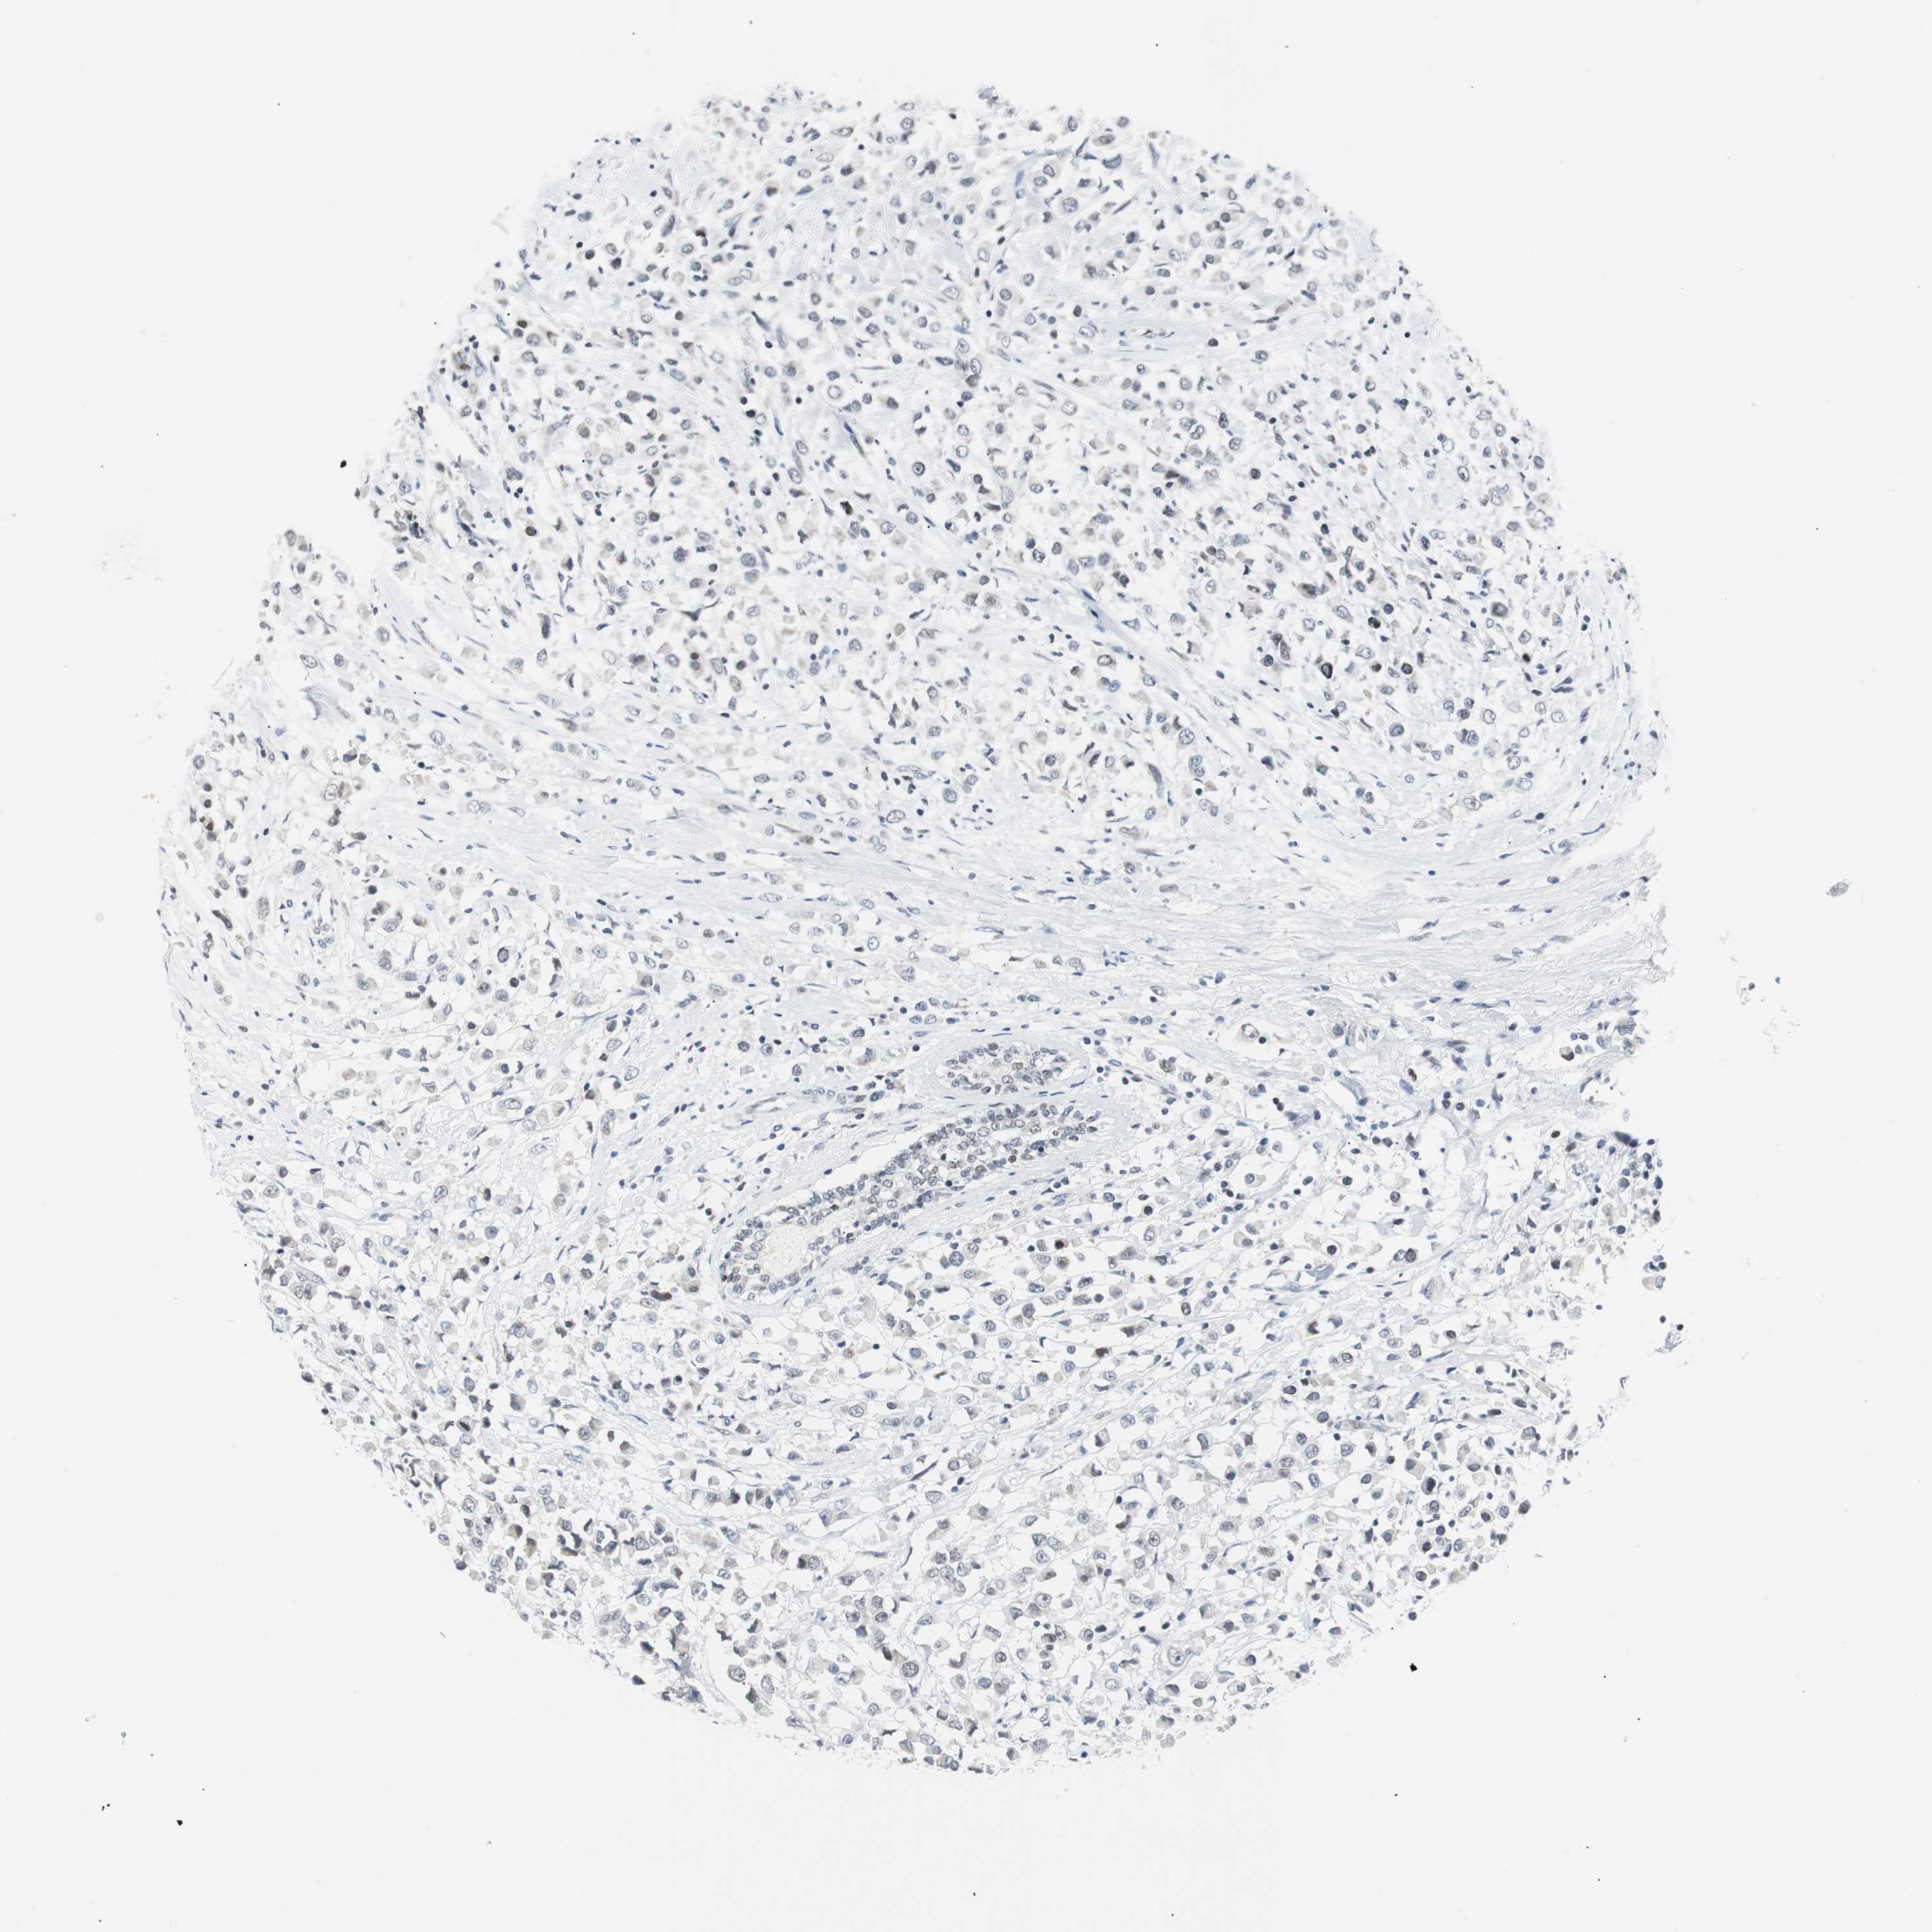

CANCER BREAST CANCER Show tissue menu

BRCA TCGA BRCA VALIDATION PROTEIN EXPRESSION